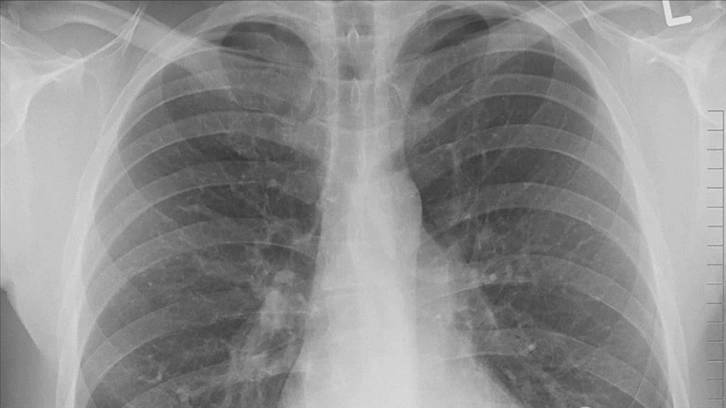

Genellikle akciğer kanserinin neden olduğu bulgu ve şikayetlerin oluşumu birkaç yıl alıyor ve bu nedenle hastalık ileri evreye gelinceye kadar fark edilemeyebiliyor. Kontrol veya başka bir rahatsızlık nedeniyle çekilen akciğer grafisinde kanser teşhis edilebiliyor, erken teşhis tedavide başarı olasılığını artırıyor.